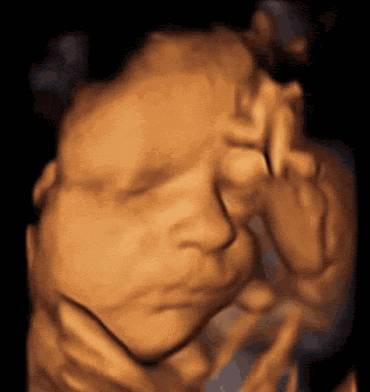

排查胎儿先天畸形;显示清晰,可以看到胎儿脸部表情、四肢动作,甚至打哈欠、伸舌头等画面。

在这个孕周阶段,胎儿生殖器官发育基本完成,从图像上能较清晰地分辨男孩或女孩的外生殖器,医生有一定判断依据。